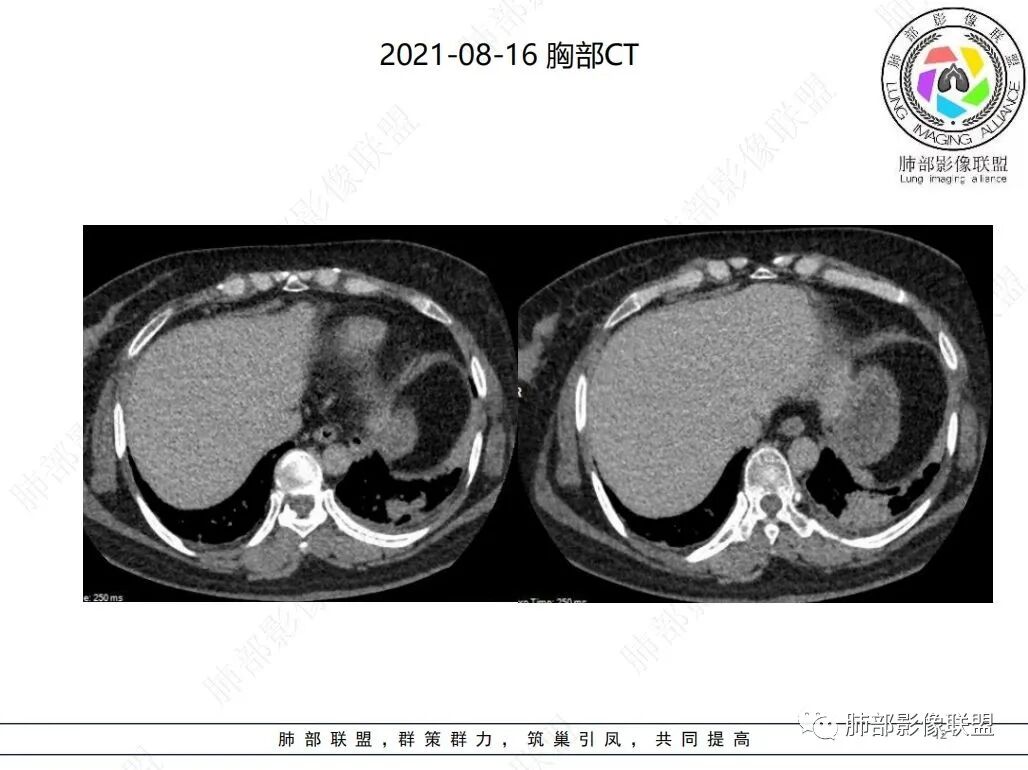

3. 病灶在外周胸膜下为主,小叶间隔增厚,支气管壁增厚,部分细支气管可见闭塞,左肺下叶实变影。合并有鼻窦炎及肾功能不全,抗感染无吸收。

4. 抗中性粒细胞胞浆抗体(ANCA)相关性血管炎(AAV)是以坏死性炎症为特点的血管炎,缺乏免疫复合物沉积,以小血管壁的炎症和纤维素样坏死为主要特征的系统性自身免疫性疾病主要累及小血管,即毛细血管、小静脉、小动脉和微动脉。肺、肾、上呼吸道、皮肤、神经系统等多系统均受累。

ANCA相关性血管炎肺部常被累及。最常见的为肺部结节,其中以支气管周围结节最多,其次是支气管扩张和胸腔积液以及肺出血和淋巴结肿大、肺气肿和空洞样病变等。由于肺内磨玻璃影、纤维条索影、斑片实变影、肺结节、网格状影、蜂窝状影、 肺大泡影、肺气肿、空洞、胸膜增厚、胸腔积液、 心包积液、纵膈淋巴结肿大等多种表现存在,极易误诊为肺部感染性疾病、间质性肺炎、肺结核及肺栓塞等疾病。